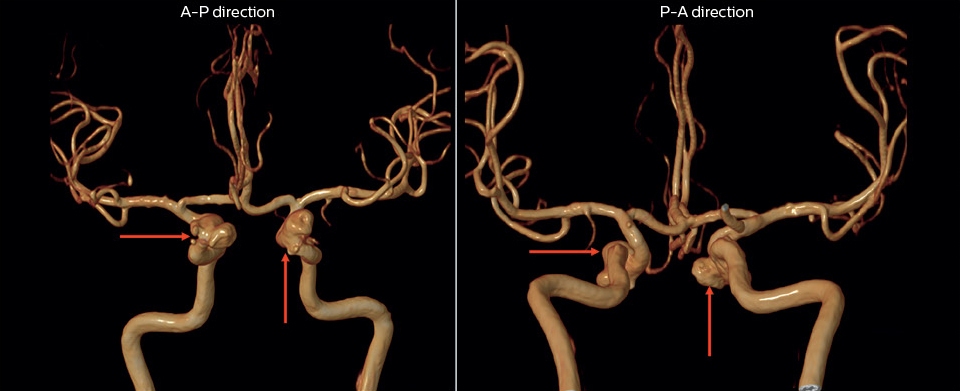

“The 3D TOF MR angiograms are obtained by using 3D T1- weighted FFE sequences (TR 35 ms, TE 7 ms, flip angle 20 degrees, field of view 250 × 190 × 108 mm, matrix 732 × 1024, four slabs, 180 slices of 0.8 mm thickness, acquisition time 8:56 minutes). On our Achieva 3.0T MRI system with an 8-channel head coil, 3D TOF is easy to use and the background signal suppression is very good. Maximum intensity projections (MIPs) and volume-rendered images are reconstructed from the data. We use a single-artery highlighting method to reduce arterial overlay. The method can also be used for carotids or other small intracranial vessels.”

“Advances in MR imaging, the high SNR and spatial resolution of 3.0T, increasing observer experience and improved postprocessing techniques have improved the capabilities of MRA over the last decade. We found that 3D TOF MRA provides excellent images for the visualization of small cerebral aneurysms which enables us to accurately diagnose, and this accuracy appears to be similar to that obtained with DSA according to data from a 2014 study," [2] Dr. Li says. “Aneurysm location can influence how easy it is recognized. Infundibula can mimic aneurysms, adding to the difficulty of interpretation. On MIP images, small aneurysms can also be easily misinterpreted when the aneurysm overlaps with the vessel. This is why in our method we are viewing the images from multiple angles.” “In the hundreds of patients with aneurysms that we scanned, we saw no significant differences in accuracy, sensitivity or specificity among the locations. [2] We think this is the result of technical advances in image acquisition and postprocessing algorithms.”

“Our high confidence in the 3D TOF MRA method was the reason to select this method for a study on the prevalence of unruptured cerebral aneurysms in Chinese adults, which involved finding the location and size of unruptured cerebral aneurysms. By the way, that study found a prevalence of 7% and most lesions had a diameter of less than 5 mm," [3] says Dr. Li.